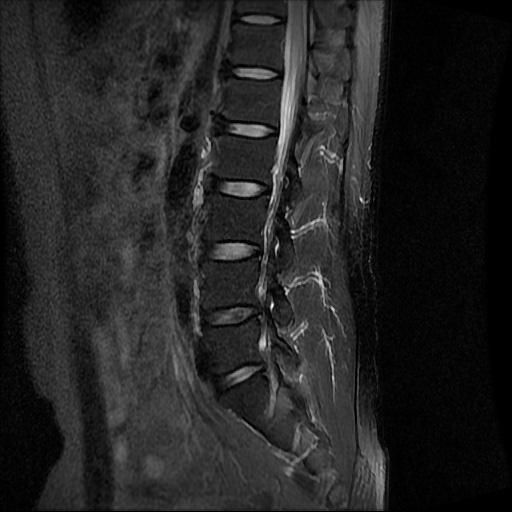

허리 MRI 디스크 상태 분석 부탁드립니다

건협에서는 관리해야 된다는데 디스크 협착이나 팽윤 등이 있는 상태인지 궁금합니다.

우선 현재로썬 사진만으론 판단을 하기에 제한이 되지만 사진상 디스크 상태는 심해보이지 않습니다.

요추부위의 하부 에서 약간의 팽윤이나 돌출로 의심해볼수 있는 정도이지만, 정확한 상태는 관련 전문의에게 진료시 문의를 하시는 것을 추천드립니다.